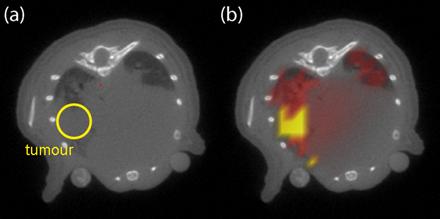

Bild für EU-Projekt 2B

Größe: 10.0 kB; available sizes 64x32  119x59  120x60  239x119  440x219